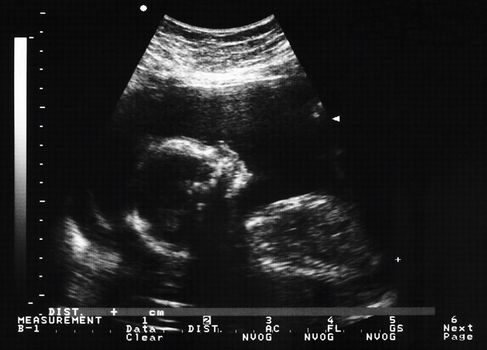

PORTLAOISE: 30 baby deaths to be investigated by the HSE

The deaths of more than 30 babies at the Midlands Hospital in Portlaoise are to be investigated by the HSE.

A panel set up to look into a number of birth complaints at the hospital is said to have examined up to 80 baby deaths, 30 of which, it was decided, required further examination, according to a Sunday Independent report.